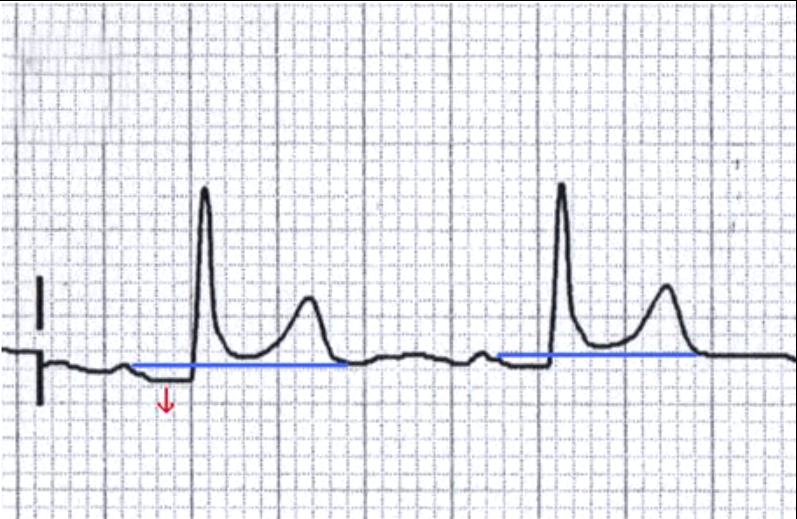

3.6. Đoạn ST

- ST bình thường là đẳng điện

- Thay đổi liên quan đến tổn thương mới cơ tim hoặc viêm màng ngoài tim; phì đại thất; thuốc digoxin

- Có thể chênh lên; chênh xuống...

- Các hình dạng khác nhau, các vị trí khác nhau cho phép chẩn đoán bệnh.